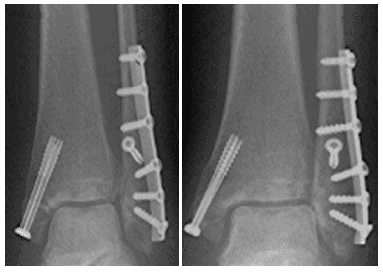

Bong gân ở mắt cá chân có thể dẫn đến sưng vào ban đêm, cũng như các chấn thương phổ biến khác ở mắt cá chân như gãy, rách dây chằng hoặc chấn thương ở dây thần kinh. Người bệnh thường cảm thấy đau ở mắt cá chân, đi lại khó khăn, cứng khớp. Bong gân chỉ cần điều trị bằng cách nghỉ ngơi, chườm lạnh. Nếu tình trạng này nghiêm trọng hơn, người bệnh có thể sẽ phải băng bó cố định, dùng thuốc để giảm sưng và tập vật lý trị liệu.